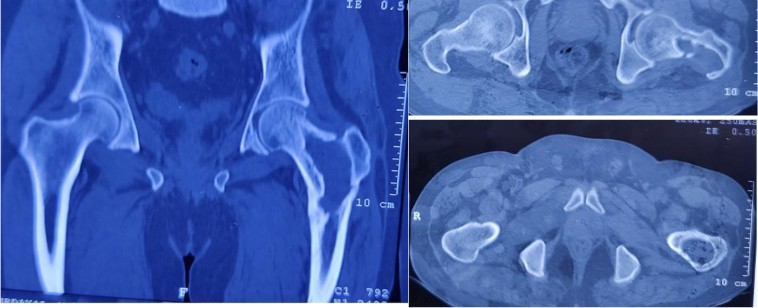

Figure 2: The computed tomography scan shows the lytic lesion in the left femur neck and trochanteric region during osteomyelitis.